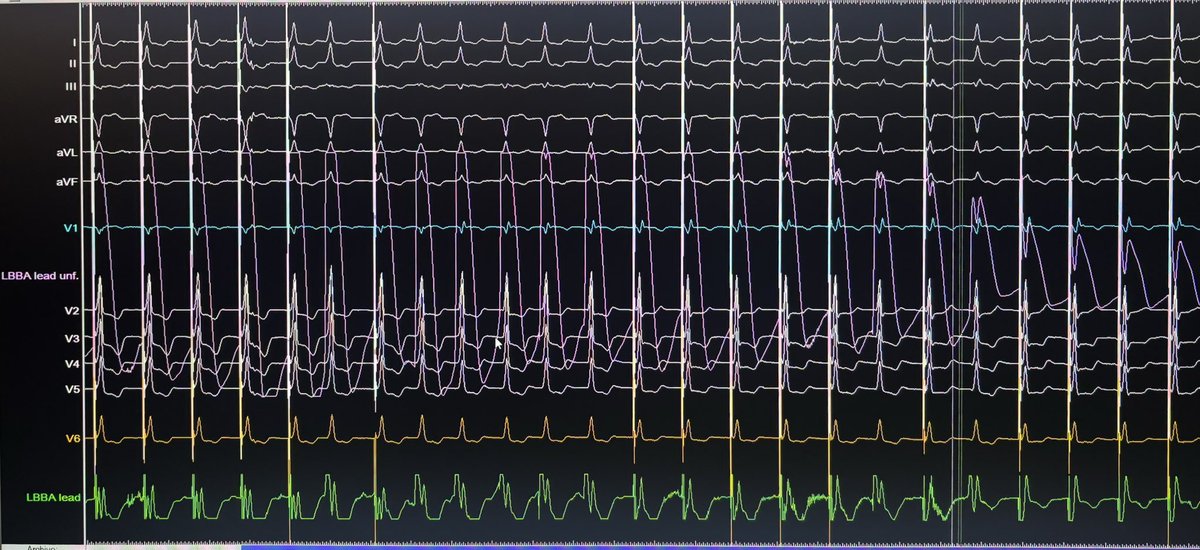

Accelerated atrial pacing reduces left-heart filling pressure: a combined clinical-computational study. Read more in #EHJ 👉 bit.ly/3BfKXhc